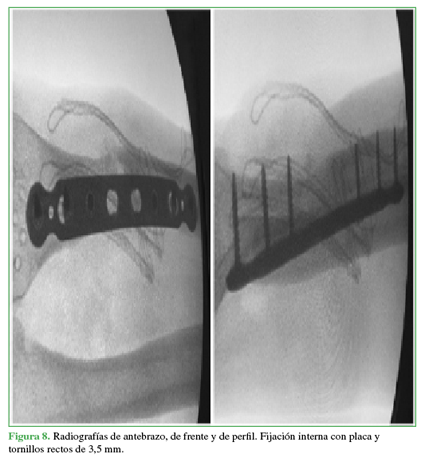

Ante los resultados negativos de las muestras de tejido enviadas a bacteriología y la seudoartrosis recalcitrante de radio, se realizó una nueva intervención con revisión y desbridamiento fibroso del foco óseo, estabilización con placa recta de 3,5 mm de diámetro y relleno con injerto óseo molido alógeno del banco de tejidos (Figura 8).